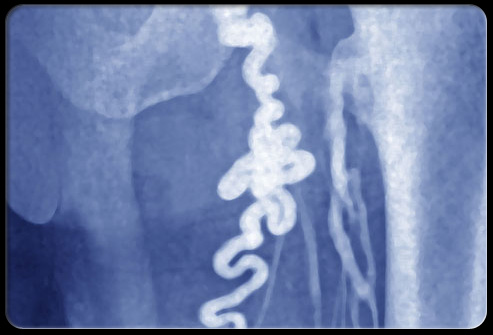

肾结石

盆腔疼痛怎么引起的,盆腔疼痛是什么原因引起的

肾结石是在肾脏或输尿管中形成的洁净;大多数肾结石都很小,不过有些肾结石可以达到高尔夫球的大小。大多数小结石会在通过输尿管时刺激输尿管并导致剧烈疼痛。患者的小编中可能带血。虽然大多数小于6mm的肾结石都能自主通过,不过过程很疼。有些结石特别是会碍事的结石需要泌尿医生进行评估是否需要碎石或手术移除。